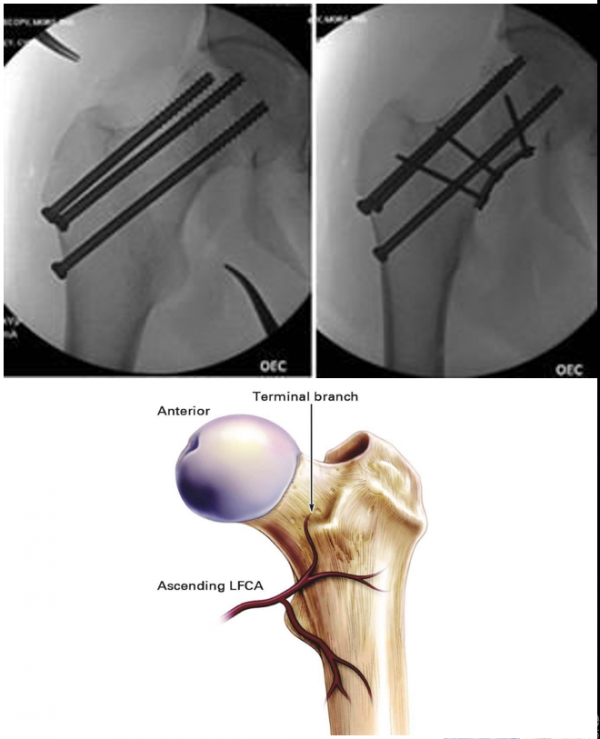

1. 三枚空心螺钉内固定

多用于新鲜青壮年股骨颈骨折;三角形平行螺钉抗拔出及抗剪切能力较弱;“正/倒三角”空心螺钉对于剪切型股骨颈骨折均存在较高失败率。

原因:螺钉的角度稳定性较差,不能对抗此型骨折负重时所产生的强大剪切力(图中f为螺钉所受剪切力,e为负重的应力)。

4. 四枚钉布钉格局(横钉或菱形理念)更符合生物力学要求;具有对抗剪切力、张力及内翻趋势;